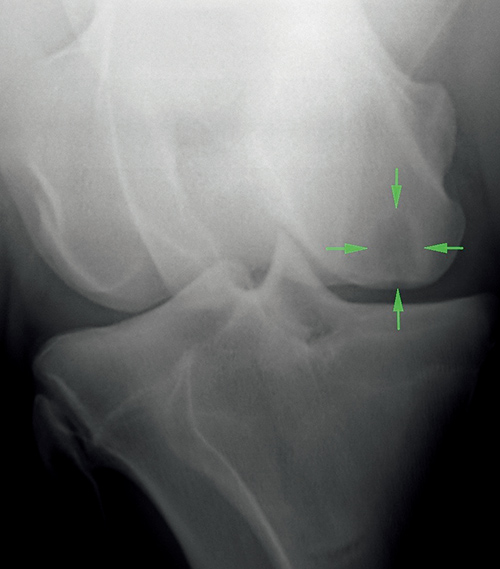

其次,獸醫(yī)檢查的另一個(gè)主要部分,就是 X光檢查。在所有重要的國(guó)際拍賣(mài)會(huì)上,馬匹X 光片隨時(shí)可供,新西蘭純血馬公司擁有一個(gè)在線資源庫(kù),獸醫(yī)可以在其中查看 X 光片。X 射線是一組標(biāo)準(zhǔn)的數(shù)字圖像,包括一歲幼馬的兩前蹄、球節(jié)、腕關(guān)節(jié)、跗關(guān)節(jié)和膝關(guān)節(jié)。

通過(guò) X 光片,獸醫(yī)可以確定任何未來(lái)可能導(dǎo)致跛行的重大隱患。一歲純血馬 X 光片中最常見(jiàn)的問(wèn)題包括膝關(guān)節(jié)囊腫,碎骨片和關(guān)節(jié)炎,這些都有可能是馬匹開(kāi)始訓(xùn)練后發(fā)生問(wèn)題的潛在因素。查閱 x 光片之后,獸醫(yī)會(huì)和你討論他的發(fā)現(xiàn),并給出馬匹發(fā)生潛在問(wèn)題的風(fēng)險(xiǎn)預(yù)估系數(shù)。

上圖:一歲純血馬的膝關(guān)節(jié) X 光。

綠色的箭頭指出有一個(gè)大的骨囊腫,當(dāng)這匹一歲純血馬開(kāi)始訓(xùn)練后很有可能會(huì)變?nèi)场?/font>